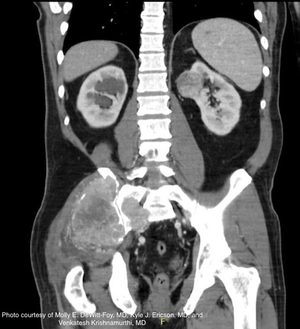

The authors discuss the case of a 57-year-old man who initially presents to a general surgeon with a chief complaint of right lower back and posterior neck pain, with associated soft tissue swelling. On presentation to the authors' institution, he had experienced regrowth of the masses with "ticking" in the right lumbar area that he correlated with his heartbeat. He also reported unintentional weight loss of 15 pounds over the previous 3 months.